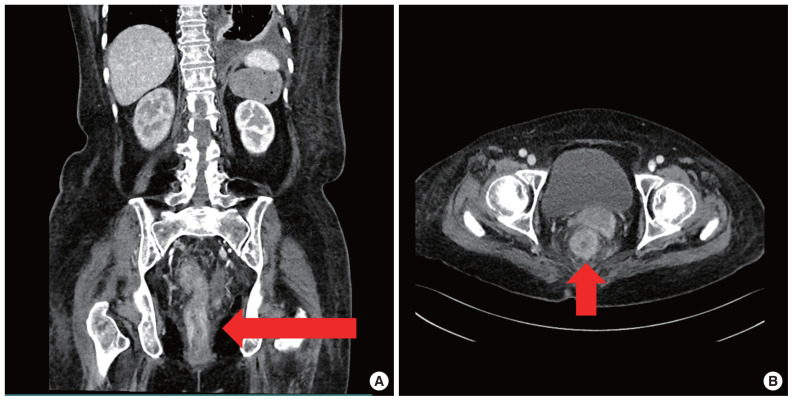

Breast cancer is the most common cancer among women worldwide. Breast cancer often metastasizes to the regional lymph nodes, bone, brain, liver, and lungs, whereas gastrointestinal tract metastases are rare. Herein, we present a rare case of rectal metastasis from breast cancer that occurred during palliative chemotherapy. A 69-year-old female with a history of invasive ductal carcinoma, negative for hormonal receptors and positive for human epidermal growth factor receptor 2 (HER2) receptor, underwent various treatments, including neoadjuvant chemotherapy, breast-conserving surgery, and adjuvant therapy. Eight months postoperatively, the patient experienced axillary lymph node recurrence, requiring palliative chemotherapy. Despite ongoing treatment, metastatic lesions were confirmed in the lungs and pleura. During palliative chemotherapy, the patient developed anal pain, and subsequent examination revealed an infiltrating rectal lesion. Despite histological confirmation of metastatic breast carcinoma and tubular adenoma, a multidisciplinary decision was made regarding palliative chemotherapy over surgical intervention. Eribulin was administered, but due to the patient's inability to tolerate the treatment, she passed away 3 months after rectal lesion diagnosis. Although breast cancer metastasis to the rectum is rare, clinicians should consider the possibility of rectal involvement and perform a digital rectal examination if anal symptoms are present.